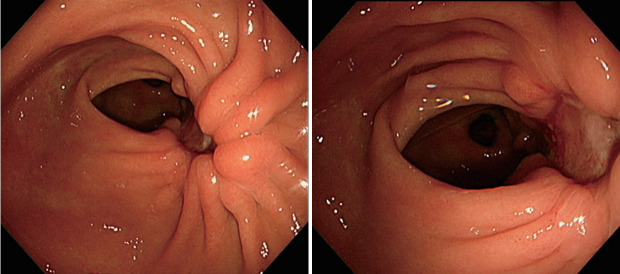

Kalimate(聚苯乙烯磺酸钙)是一种阳离子交换树脂,常用于临床治疗高钾血症。然而,Kalimate已被证明也会导致严重的胃肠道损伤,如结肠坏死、溃疡和穿孔,在慢性肾功能衰竭患者的亚群中;这些病例的报告有高渗山梨醇的管理和不。这些病变通常发生在大肠或小肠;发生在胃的病变很少被报道。我们报告了一名62岁的妇女,她患有非常大的Kalimate诱发的胃溃疡,被误诊为晚期胃癌的慢性肾衰竭患者,她已经服用了Kalimate 3个月。患者通过停用Kalimate和启动质子泵抑制剂成功治疗。

Kalimate (calcium polystyrene sulfonate) is a cation-exchange resin commonly used in clinical practice to treat hyperkalemia. However, Kalimate has been demonstrated to also cause serious gastrointestinal injuries, such as colonic necrosis, ulcerations, and perforations, in a subset of patients with chronic renal failure; these cases have been reported with and without the administration of hypertonic sorbitol. These lesions usually occur in the large or small intestine; lesions occurring in the stomach are rarely reported. We present the case of a 62-year-old woman with very large Kalimate-induced gastric ulcers that were mistaken for advanced gastric cancer in patients with chronic renal failure who had been taking Kalimate for the previous 3 months. The patient was successfully treated by discontinuing Kalimate and initiating a proton pump inhibitor.